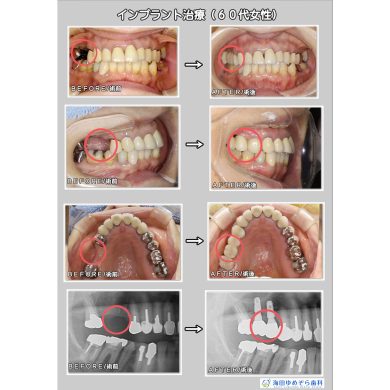

インプラントの症例 GBR法/骨補填材使用

☆治療内容

インプラント

☆治療期間

2年2ヶ月

☆治療費用

¥440,000×2本 + GBR人工骨\110,000

総額\990,000(税込)

☆リスク

術後の出血、腫れ、痛みの可能性があります